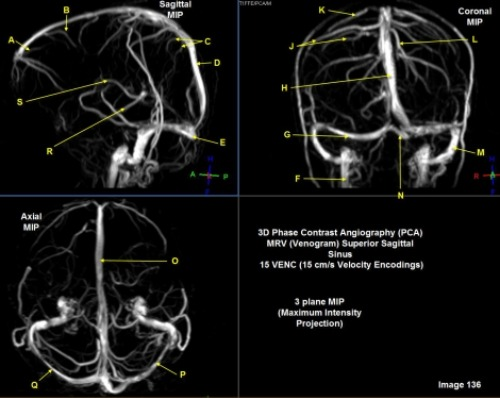

Letter C in Image 136 is pointing to:

A. Anterior frontal veins

B. Posterior frontal veins

C. Parietal veins

D. Internal cerebral veins

E. Vein of trolard

Letter Q in Image 136 is pointing to:

A. Right transverse sinus

B. Left transverse sinus

C. Right parietal veins

D. Left parietal veins

E. Right sigmoid sinus

F. Left sigmoid sinus

Letter F in Image 136 is pointing to:

A. Anterior frontal vein

B. Posterior frontal vein

C. Parietal vein

D. Internal jugular vein

E. Internal cerebral vein

Letter D in Image 136 is pointing to:

C. Sigmoid sinus

D. Superior sagittal sinus

Letter J in Image 136 is pointing to:

Letter M in Image 136 is pointing to:

Letter R in Image 136 is pointing to:

A. Rosenthal vein

C. Basal vein

D. Internal cerebral vein

F. A and / or C

Letter P in Image 136 is pointing to:

Letter G in Image 136 is pointing to:

A. Superior sagittal sinus

B. Right sigmoid sinus

C. Left sigmoid sinus

D. Right transverse sinus

E. Left transverse sinus

Letter K in Image 136 is pointing to:

Letter E in Image 136 is pointing to:

B. Vein of trolard

C. Torcular herophili

E. Posterior sigmoid sinus

Letter B in Image 136 is pointing to: